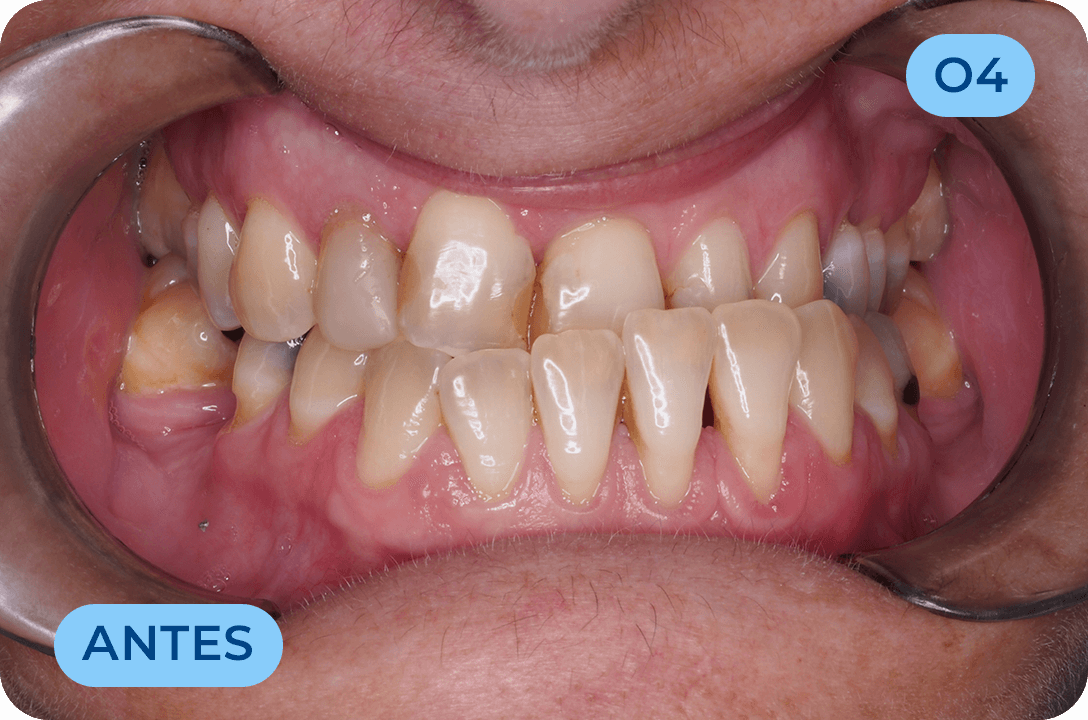

Prostodontia

É a área da Medicina Dentária que atua na substituição de dentes perdidos ou comprometidos esteticamente. Os dentes são substituídos através de dentes fixos (coroas em cerâmica suportadas por implantes ou suportadas por raízes de dentes naturais) bem como próteses removíveis. Mais recentemente surgiram as facetas (lentes de contacto) com a vantagem de conservar mais os tecidos dentários e com ótimos resultados estéticos. É uma área muito importante na reabilitação da função mastigatória assim como da auto estima, recuperando a vontade de sorrir.